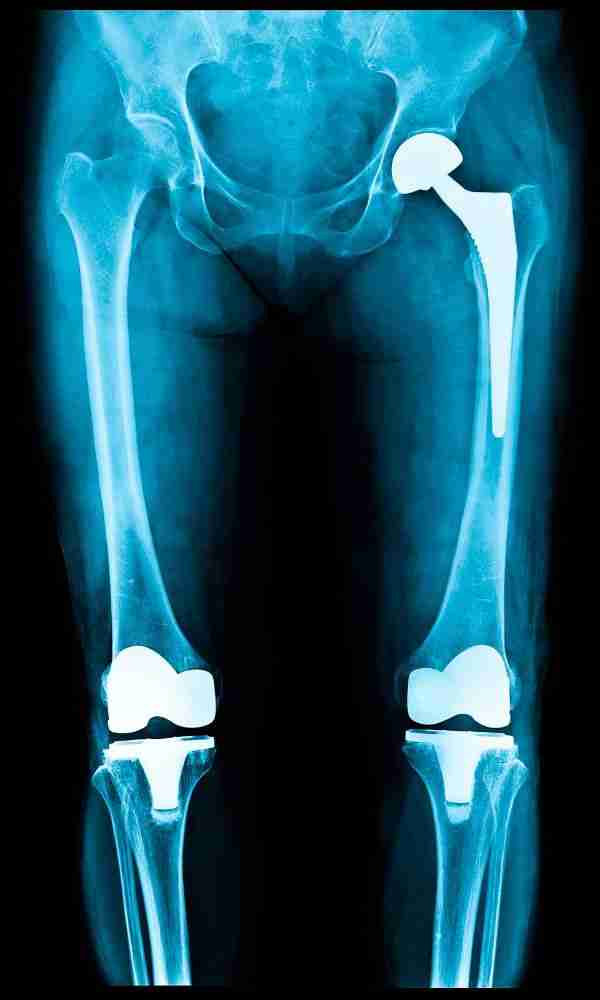

Hip or knee replacement surgery is a transformative procedure that can significantly improve the quality of life for individuals with severe arthritis or joint damage. However, the financial aspect of these surgeries is an important consideration. Understanding your expected bills is crucial for effective planning and decision-making.

Implant Costs

Implants are a significant component of the total cost, with prices varying based on material and design.

- Hip Implants: $4,000 to $7,000.

- Knee Implants: $4,500 to $8,500.